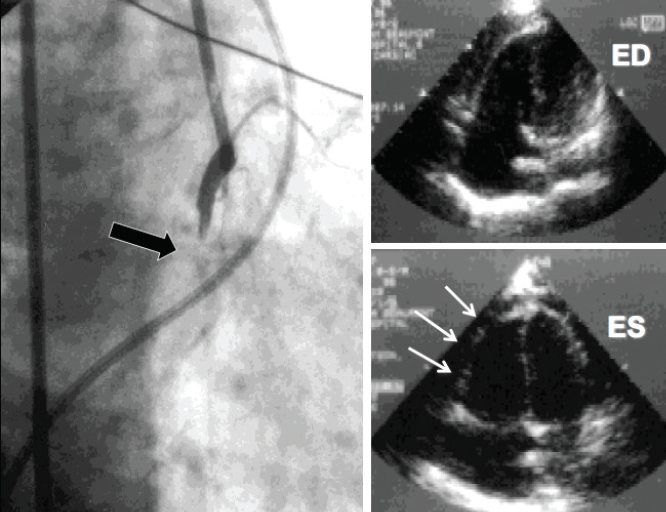

Figure 2. Invasive hemodynamic tracings of a patient who was initially treated with a percutaneous LVAD for LV failure (A). The patient became hypotensive, and based largely on the invasive hemodynamic data, an Impella RP device was inserted (B), resulting in improved cardiac output and reduced right atrial pressure (C). PCW, pulmonary capillary wedge.

Although VA-ECMO “bypasses” both the left and right ventricles, it has limited utility in the treatment of biventricular failure because the anticipated LV afterload will worsen LV hemodynamics without an additional MCS device to unload the LV. However, direct RV support devices in combination with either direct LV support devices (Impella, TandemHeart) or IABP have been used to successfully treat biventricular failure as a bridge to recovery, durable circulatory support, or cardiac surgery (Figure 2).26-31